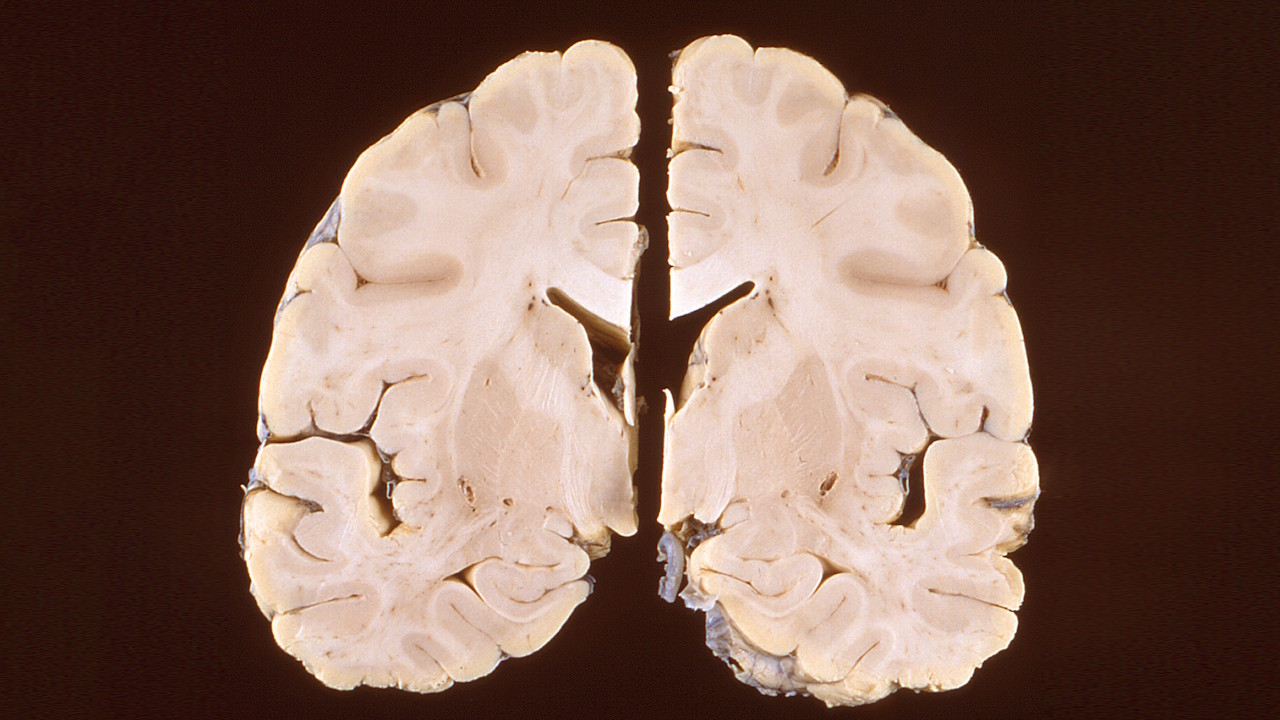

Зріз мозку людини з вірусним захворюванням нервової системи. На відміну від шизофренії та біполярного розладу, інфекційні захворювання залишають у мозку чіткі сліди, які можна використати для їхньої діагностики. CDC / Brian W.J. Mahy